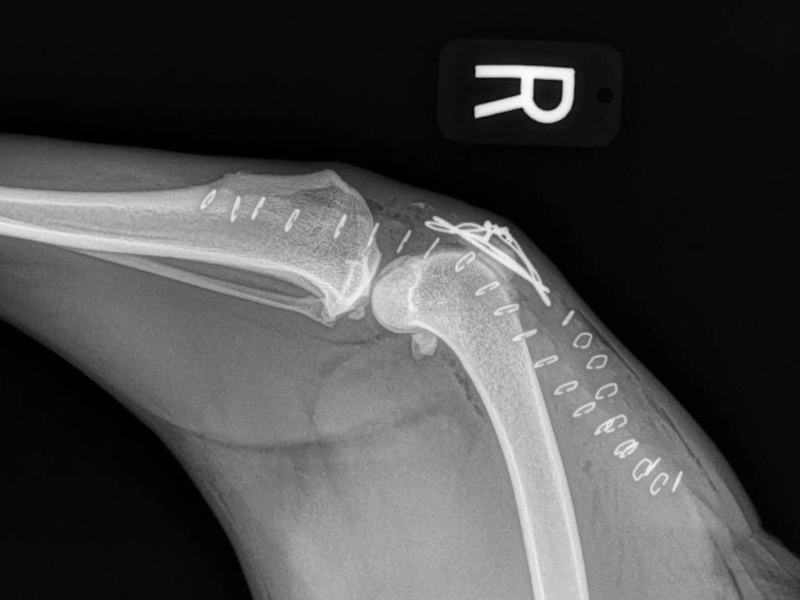

Tibial Plateau Leveling Osteotomy (TPLO) - additional information

An osteotomy is a surgical cut in a bone. In the cruciate deficient stifle, a cut is made in the top of the tibia. The top portion of bone that contains the articular surface is rotated to level it. The two pieces of bone are held in place with a metal plate and screws.

Post Surgical Radiographs

While the patient is still anesthetized, the patient is taken into radiology for post-surgery radiographs (X-rays). The radiographs are assessed to measure the new tibial plateau angle. We are aiming for 5-6 degrees relative to the long axis of the tibia. The apparatus (plate and screws) are assessed for size and appropriate position.